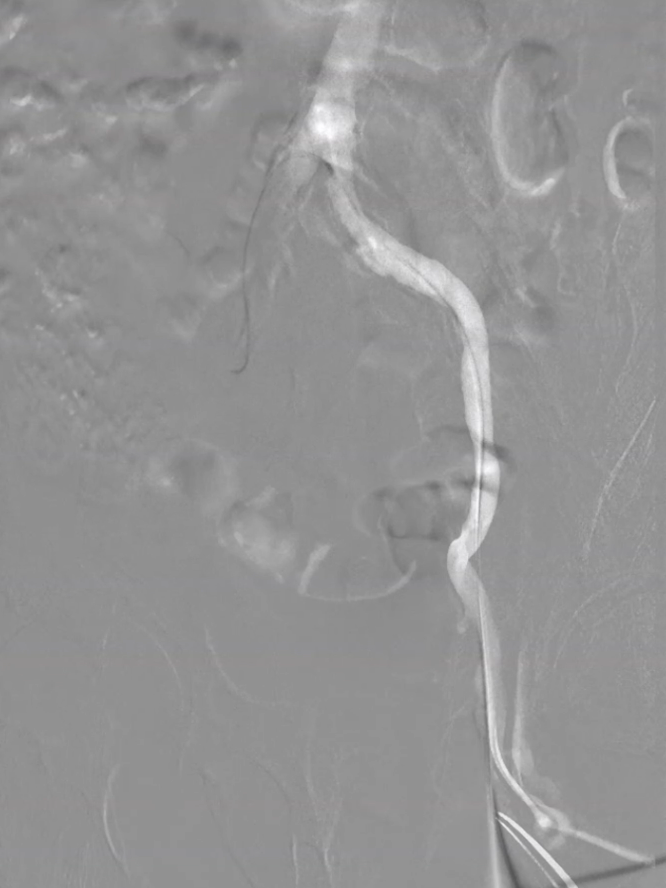

步进造影:股浅动脉起始重度狭窄、中段重度狭窄,腘动脉远端重度狭窄、胫前动脉、胫后动脉闭塞

V-18导丝配合多功能导管通过股浅动脉、腘动狭窄闭塞段,交换0.14导丝远端置于腓动脉中段

经导丝送入IVUS导管,股浅动脉近段重度狭窄、钙化明显,狭窄率大于90%

股浅动脉中远段及腘动脉重度狭窄、环周钙化明显

因患者股浅动脉及腘动脉狭窄闭塞段均严重钙化,选择使用振波球囊(6mm*80mm、5mm*80mm)

分别对股浅动脉、腘动脉狭窄闭塞段扩张(球囊至4atm,3级振波强度3个循环,5级振波强度3个循环);球囊切迹逐渐消失